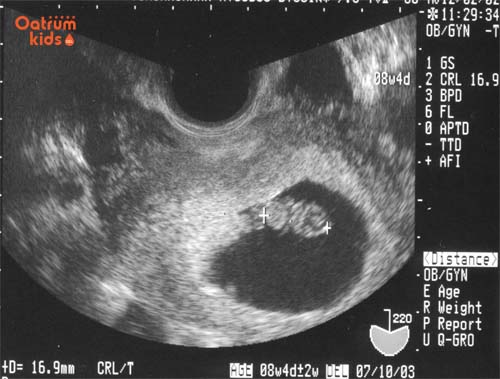

Khi thai nhi 8 tuần tuổi thì mẹ đi khám thai và làm các xét nghiệm quan trọng như: siêu âm 2D để kiểm tra tim thai, kiểm tra nội tiết, khám thai. Ngoài ra nhớ bổ sung vi chất dinh dưỡng, uống sắt, canxi cùng axit folic để giúp con tăng trưởng tốt.